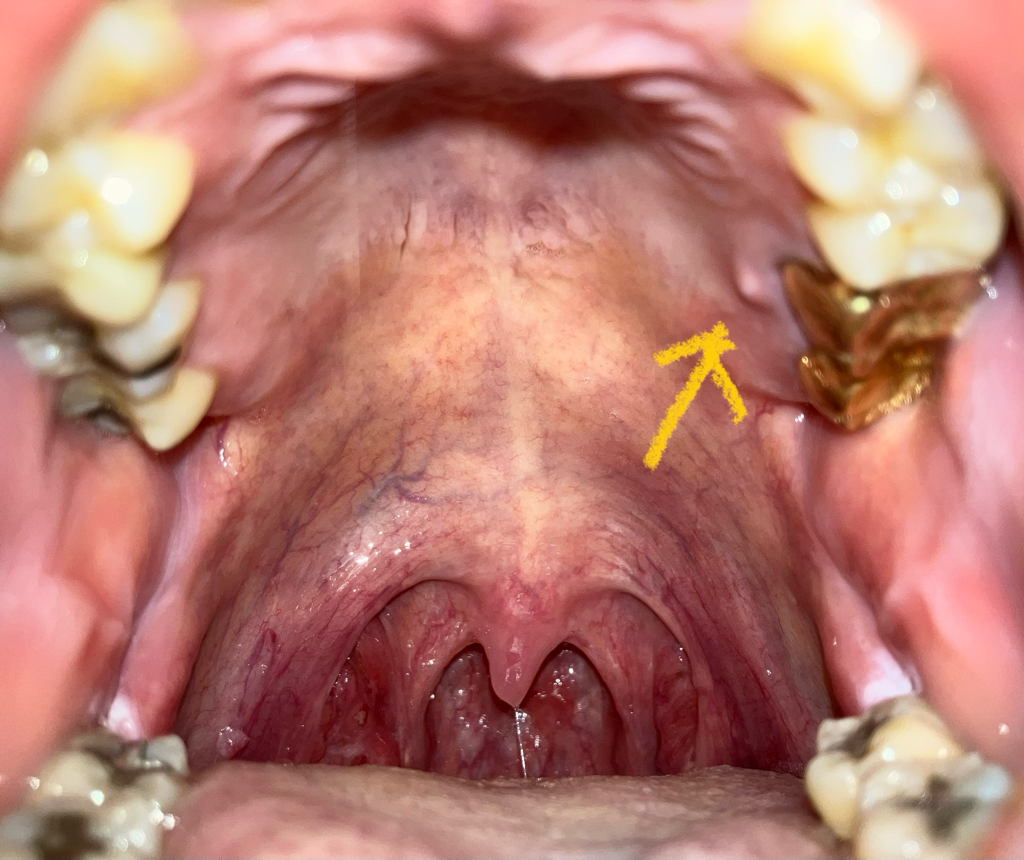

치아내부의 신경관에 감염이 생기게 되면 치아의 뿌리 끝에 고름이 차게 되고 시간이 지나면서 잇몸밖으로 나오게 됩니다.

이런경우에는 해당치아를 신경치료해서 염증을 줄일수 있습니다.

아마도 치아 뿌리끝에 염증이 생긴거 같습니다. 신경치료를 해야될수도 잇으니 치과에 가셔서 검진을 받아보세요.

잇몸에 염증이 생긴 상태입니다. 염증이 어디서 비롯되었는지를 먼저 파악해야 합니다. 만약 잇몸에서 비롯되었다면 잇몸치료를, 치아의 신경(치수)에서 기원한 염증이라면 어느 치아인지 먼저 파악해야하고 그 다음 필요하다면 신경치료를 진행합니다. 주변 크라운으로 씌운 치아가 신경치료가 안되어 있다면 크라운을 뜯고 신경치료를 해줍니다. 신경치료가 이미 되었다면 재신경치료 또는 치근단절제술을 시행하게 됩니다.